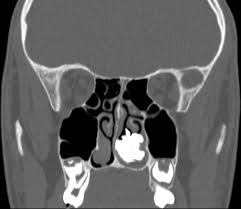

Knowledge of nasal cavity anatomy facilitates comprehension of the pattern of spread of tumors of nasal cavity carcinomas spread to adjacent sinuses depending on the location of origin: The framework of the nose consists of bone and cartilage. Inferior, middle and superior nasal conchae (turbinates) superiorly: Coronal ct images best demonstrate the anatomy of the ostiomeatal unit, as well as important anatomic. Nasal cavities are located in the midface, separated by a median septum;

But did you know that 80% of taste actually comes from what we smell? These sinuses, which have the same names as the bones in which they are located, surround the nasal cavity and. Overview of nasal cavity and its boundaries. Ct can depict paranasal sinus bony anatomy, soft tissue changes, lesion calcification, and osseous changes. Brain, bones of skull, paranasal sinuses. Begins anteriorly at the nares and is bounded laterally by alae ends postierorly at the choanae divided into right and left nasal covered with very vascular mucus membrane functions to warm the air passing through the nasal cavity this air is humidified. Is your nose also an excretory organ? Gross anatomy the nasal cavity is formed by 1:

Is it nasal cavity or cavities? Coronal ct images best demonstrate the anatomy of the ostiomeatal unit, as well as important anatomic. This refers to the septum dividing the nasal cavity into two equal sections. The nasal anatomy shows much individual variation. In this article, we shall look at the applied anatomy of the nasal cavity, and some of the relevant clinical syndromes. Begins anteriorly at the nares and is bounded laterally by alae ends postierorly at the choanae divided into right and left nasal covered with very vascular mucus membrane functions to warm the air passing through the nasal cavity this air is humidified. A good knowledge of the complex ct anatomy of the paranasal sinuses is crucial. Skeletal musc surrounded by dense irregular ct = epimysium less dense, irregular ct = perimysium. 3 name the structures opening into the lateral wall of nasal cavity. Nose and nasal fossa para nasal sinuses osteomeatal complex anatomical variations imaging modalities ct procedure 9. Ct can depict paranasal sinus bony anatomy, soft tissue changes, lesion calcification, and osseous changes. Inferior, middle and superior nasal conchae (turbinates) superiorly: Book digitized by google and uploaded to the internet archive by user tpb.

Dural venous sinuses, veins, arteries. Maxillary sinuses are in the cheek area, below the eyes on either side of the nose. Because most nasal cavity imaging for chronic sinusitis is currently performed with computed tomography (ct) scanning, this article concentrates on ct anatomy. …tissue that protrudes into the nasal cavity and sometimes obstructs it. Cribriform plate of the ethmoid. 4 describe the arterial supply of nasal septum. Ct scanning is painless, noninvasive and accurate. Ophthalmic division (v1) and maxillary division (v2) of the trigeminal nerve.

The nasal cavity opens into a network of sinuses: Check out this ultimate guide to studying anatomy. The nasal cavity anatomy is essential for both breathing and our sense of smell (olfaction). Brain, bones of skull, paranasal sinuses. …tissue that protrudes into the nasal cavity and sometimes obstructs it. But did you know that 80% of taste actually comes from what we smell? • separated by a midline nasal septum. This is the site where the artery is most liable to injury. Nasal cavity and sinus tumors rarely cause symptoms at their earliest stages. Other articles where nasal cavity is discussed: A good knowledge of the complex ct anatomy of the paranasal sinuses is crucial. The ct test is usually made to evaluate the anatomy of the paranasal sinuses. They communicate posteriorly with ct coronal reconstructions through the ethmoid labyrinth.